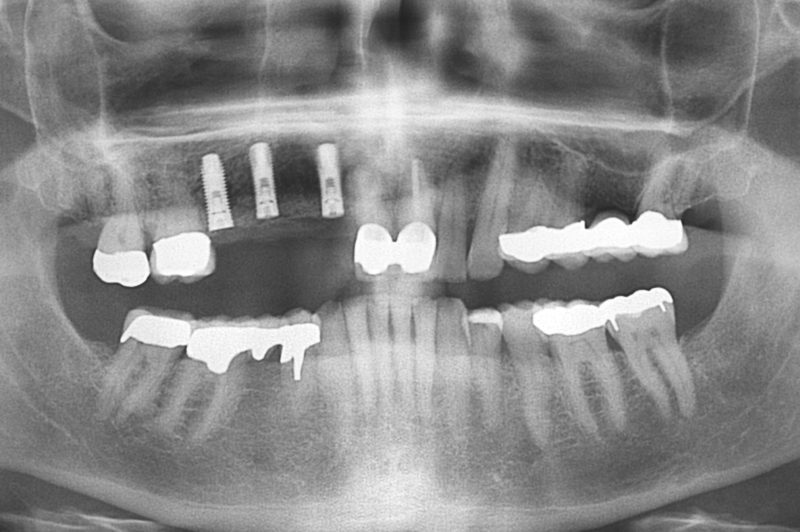

OPG of the initial situation – provision of missing denture in regio 44 to 47 by a resin-retained bridge